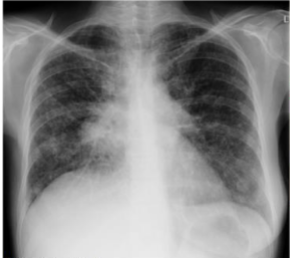

what is this?

lobar pna